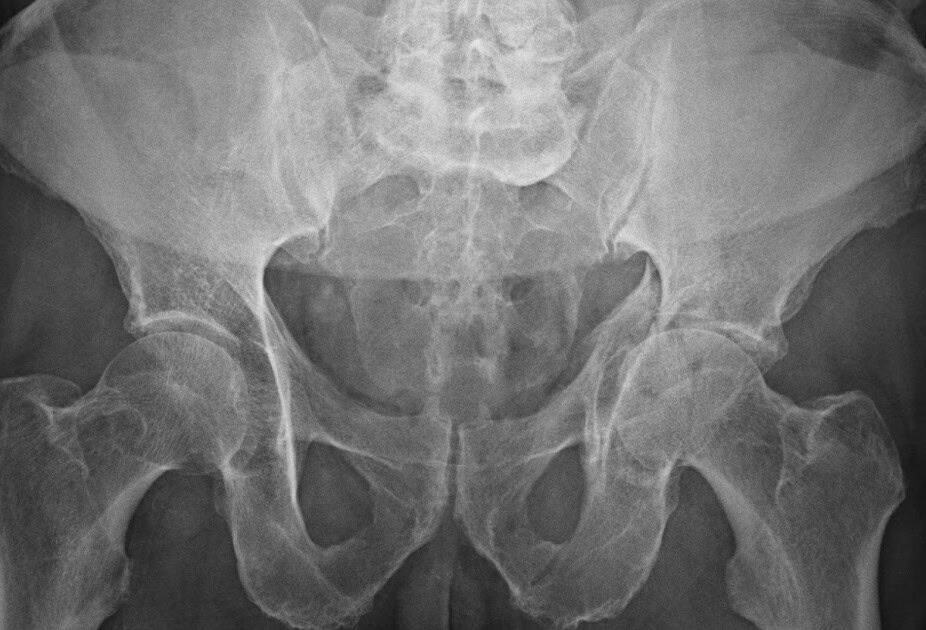

Pelvic fractures involve the bones that make up the pelvis, while acetabular fractures affect the socket of the hip joint. These injuries often occur together and can be caused by high-impact trauma such as vehicle accidents or serious falls.

Pelvic and acetabular fractures are considered serious because they can affect not only the bones and joints but also surrounding ligaments, muscles, and internal organs. Without prompt and accurate treatment, they may lead to long-term mobility problems or complications.

Treatment depends on the type and severity of the fracture. Some cases can be managed with non-surgical methods, while others require surgical intervention such as open reduction and internal fixation or minimally invasive procedures. Advanced imaging helps us decide the most effective approach.